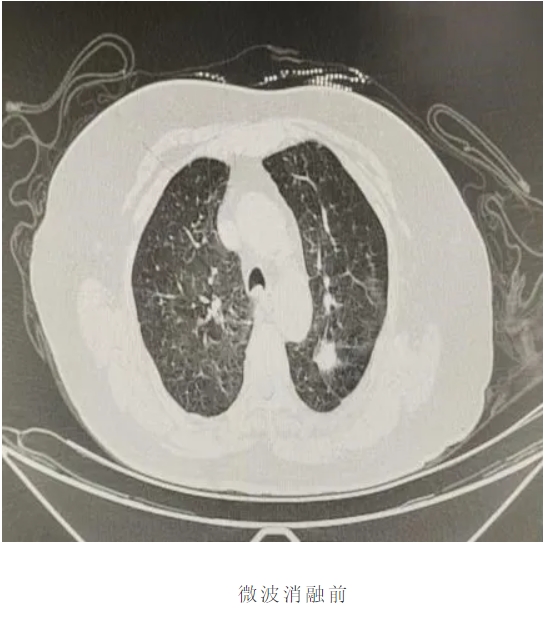

近日兴安盟人民医院胸外科团队成功完成院内首例肺结节微波消融术。在多模态影像导航系统引导下,直径仅1.8毫米的消融针如"精准导弹"直抵肺结节病灶,通过高频微波震荡产生局部高温,在数分钟内完成直径2.3厘米结节的完全灭活。同期开展的肺占位减瘤消融术,为晚期肺癌患者实现肿瘤负荷精准控制;联合实施的活检消融一体化技术,更在获取病理标本的同时完成肿瘤边缘灭活,开创"诊断+治疗"一站式微创诊疗先河。

患者老年女性,既往高血压3级很高危、阑尾术后、胆囊结石术后,多种药物过敏史,病灶位于左肺上叶。面对患者高龄、合并多系统疾病等严峻挑战,我院胸外科团队与辽宁省人民医院胸外科专家杨海涛教授深入探讨治疗方案,与患者家属充分沟通后最终决定为患者行微波消融术,术中在CT引导下精准定位靶点。面对患者高龄、合并多系统疾病等严峻挑战,我院胸外科团队与杨海涛教授深入探讨治疗方案,与患者家属充分沟通后最终决定为患者行微波消融术,术中在CT引导下精准定位靶点。